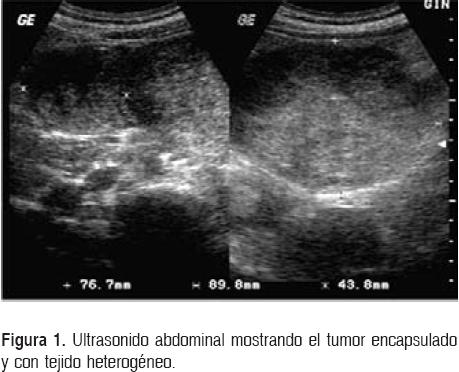

Los exámenes de laboratorio fueron normales, incluidos los niveles de α-feto-proteína y β-gonado-tropina coriónica humana. Se realizó ultrasonido que muestra lesión en cuadrante superior izquierdo, de 8 x 9 x 5 cm aproximadamente, sólido, de aspecto heterogéneo y cápsula bien definida (Fig. 1). Se realiza tomografía axial computarizada (TAC), en la que se observa un tumor de aproximadamente 8 x 8 cm, heterogéneo, bien definido por la presencia de una cápsula (Fig. 2). La imagen por resonancia magnética (IRM) de la lesión en sentido axial (Fig. 3) revela el tumor ocupando gran parte del cuadrante superior izquierdo.

Los estudios de imagenología para el diagnóstico de estas lesiones son: el ultrasonido, la tomografía axial computarizada (TAC) y la imagen por resonancia magnética (IRM). En las placas simples de abdomen pueden observarse estructuras desplazadas o calcificaciones.9 Por otra parte, en el ultrasonido se visualiza una masa con áreas de alta y baja ecogenicidad sin septos en su interior,34 y la angiografía demuestra zonas de poca vascularidad.9,38 En la TAC, los TSP se presentan como masas heterogéneas grandes con presencia de una cápsula.25 Las zonas de hemorragia tienen hiperatenuación y las áreas de degeneración quística se observan con hipoatenuación. Las calcificaciones se observan en el 30% de los casos. Con el contraste se observa un reforzamiento periférico heterogéneo con un centro de baja densidad.39 La cápsula suele ser hi-perdensa (70%) y los tumores pueden presentar un nivel líquido en su interior (10%).35 Las calcificaciones son raras, pero cuando existen, se encuentran en la periferia del tumor.40 Algunos autores han reportado una frecuencia de calcificaciones de aproximadamente 40%.23,31 En las resonancias magnéticas se muestra una heterogeneidad en 73.5% de los casos y en 89% son hiperintensas. La presencia de hemorragias dentro de la lesión se observa en más del 70% de los casos.35 Las áreas de hiperintensidad en la serie T1 y de hipointensidad baja o no-homogénea en la serie T2 ayudan a identificar las áreas de hemorragia y también ayudan a diferenciar los TSP de otros tumores pancreáticos.19 Las zonas sólidas en la serie T1 se muestran hipointensas, aunque pueden verse ocasionalmente zonas de hiperintensidad.41 Se ha sugerido realizar biopsias por punción por aspiración con aguja fina (PAAF) percutánea guiada por TAC, aunque no se ha difundido su uso debido a complicaciones potencialmente serias.37 Por ello, se ha sugerido la posibilidad de realizar biopsias por aspiración con aguja fina guiada por ultrasonido endoscópico, ya que muestran sensibilidad de 81.6% y especificidad de 87.5% para tumores no neuroendocrinos.42 Las complicaciones con este método diagnóstico apenas son del 2%.43 El TSP también se ha detectado con la tomografía por emisión de positrones; se puede observar una captura elevada de la F-18 fluorodeoxiglucosa por la lesión.44